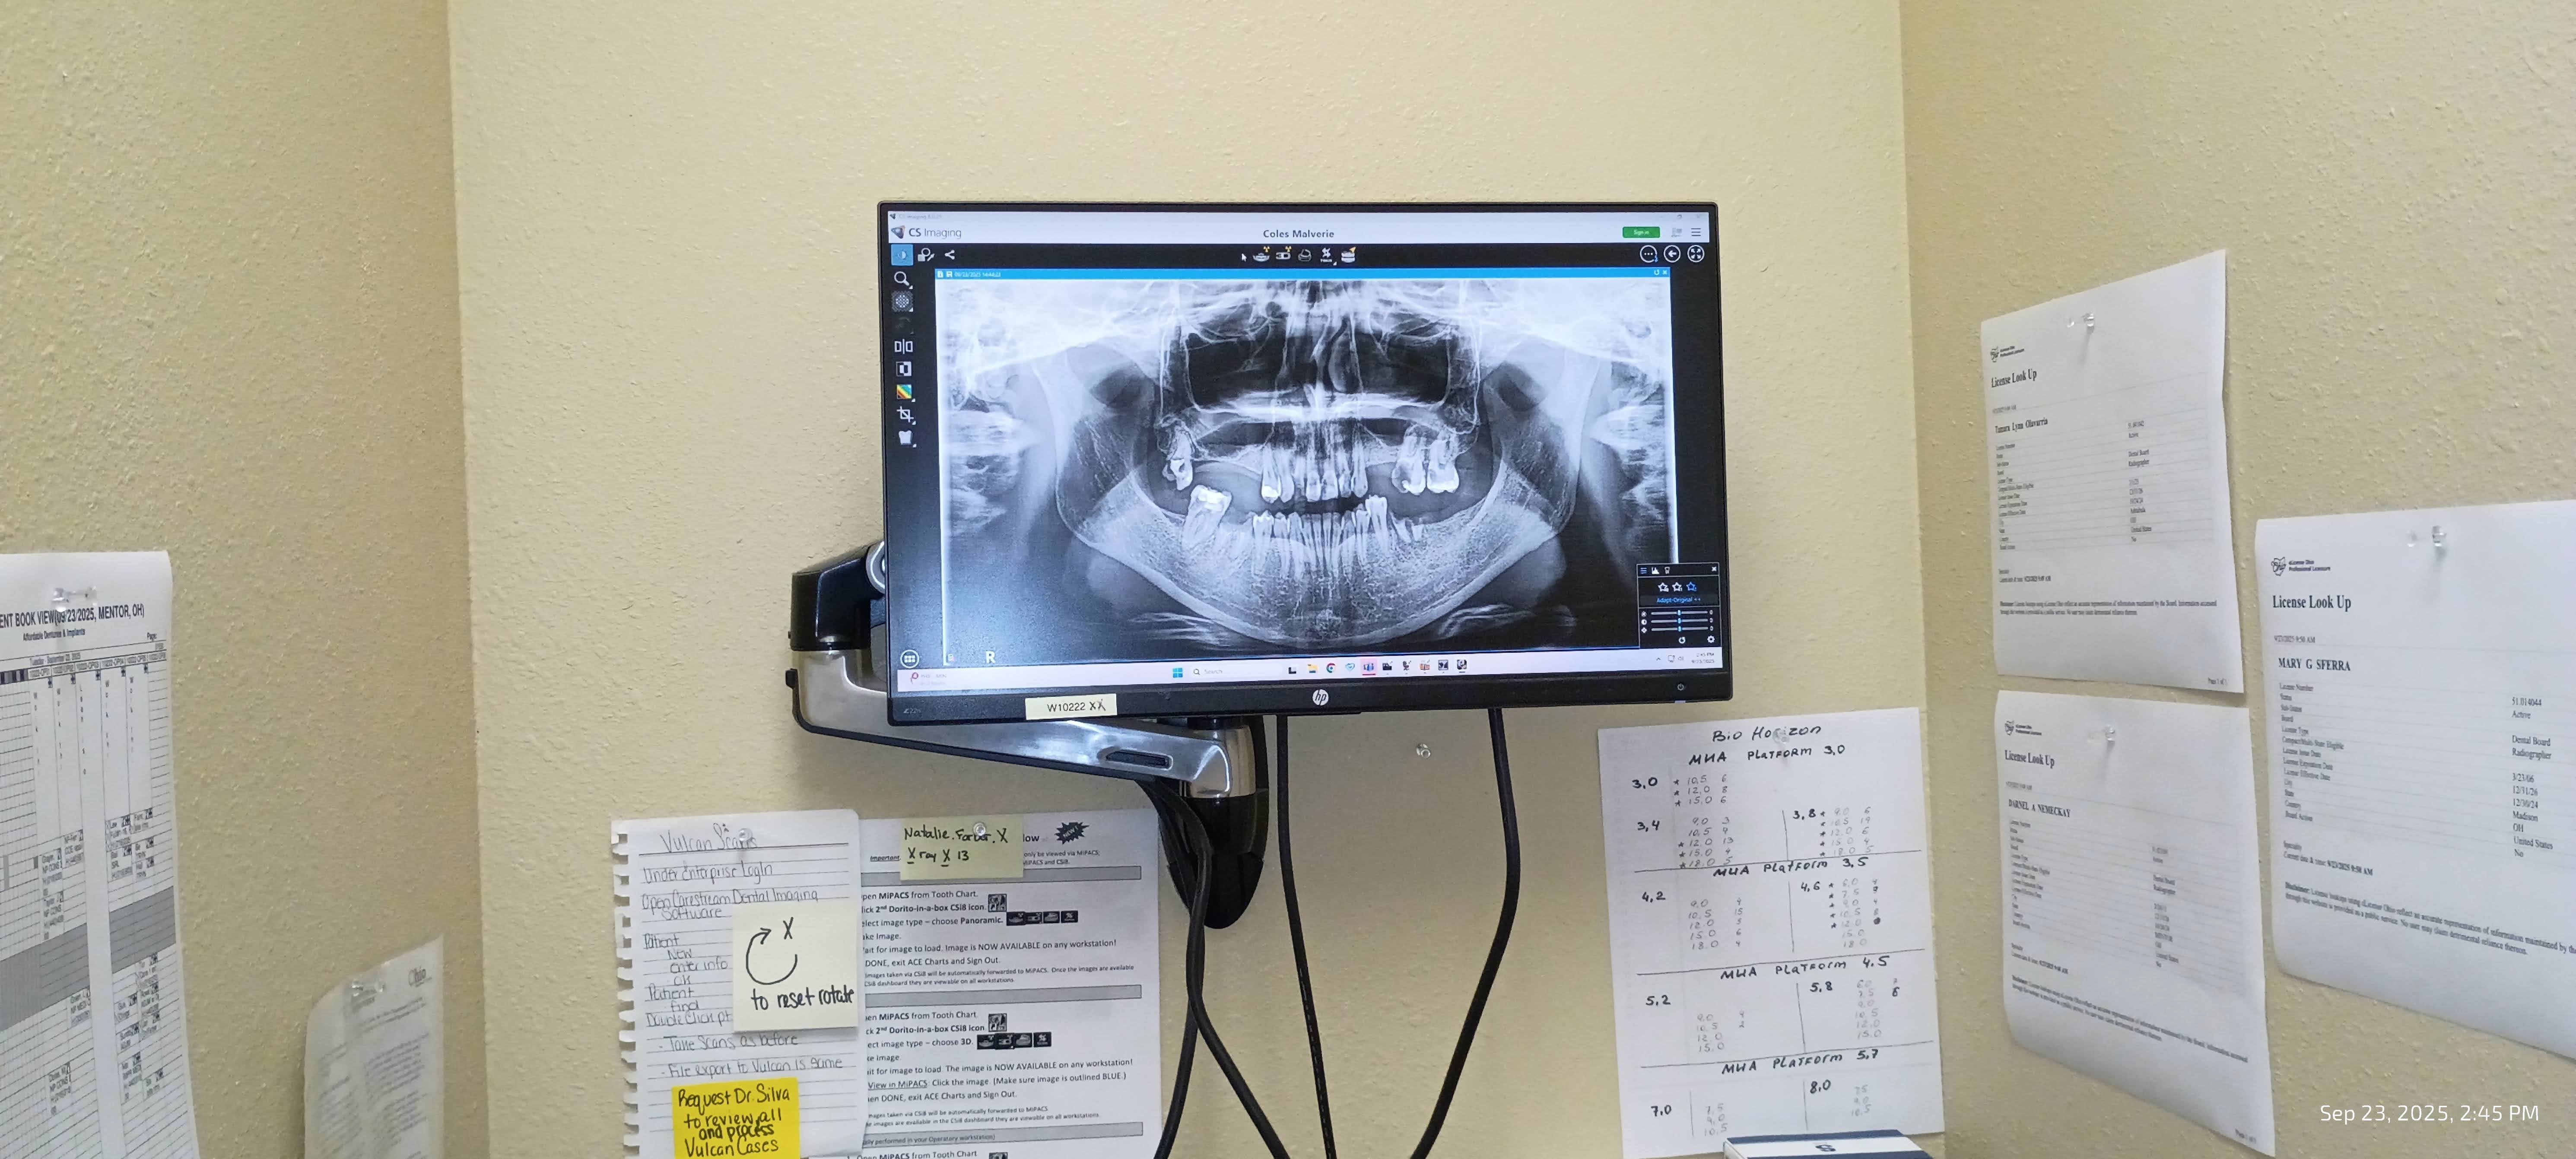

My name is Malverie, and I am reaching out to my community for support as I face a significant medical challenge. I am in need of permanent dentures or dental implants, which are essential not only for my personal confidence and oral comfort but also for protecting my oral health and potentially my overall well-being. This journey has been difficult, and the costs associated with these procedures are more than I can manage on my own.